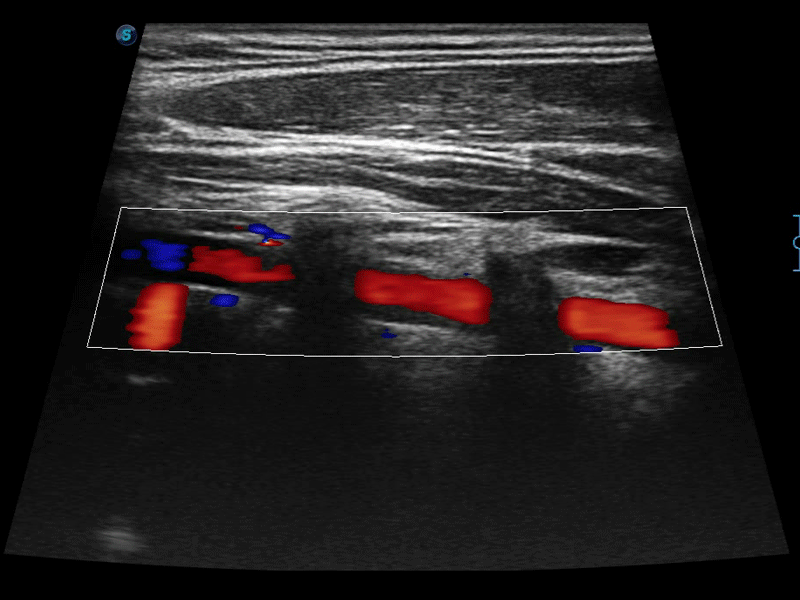

• 实时宽景成像技术

通过色彩血流和实时宽景相结合,可观察到完整的静脉或动脉的血流,方便医生检查。实时扫查过程中,如有任何操作失误也可以很容易地进行回扫擦除,而不会中断扫查。